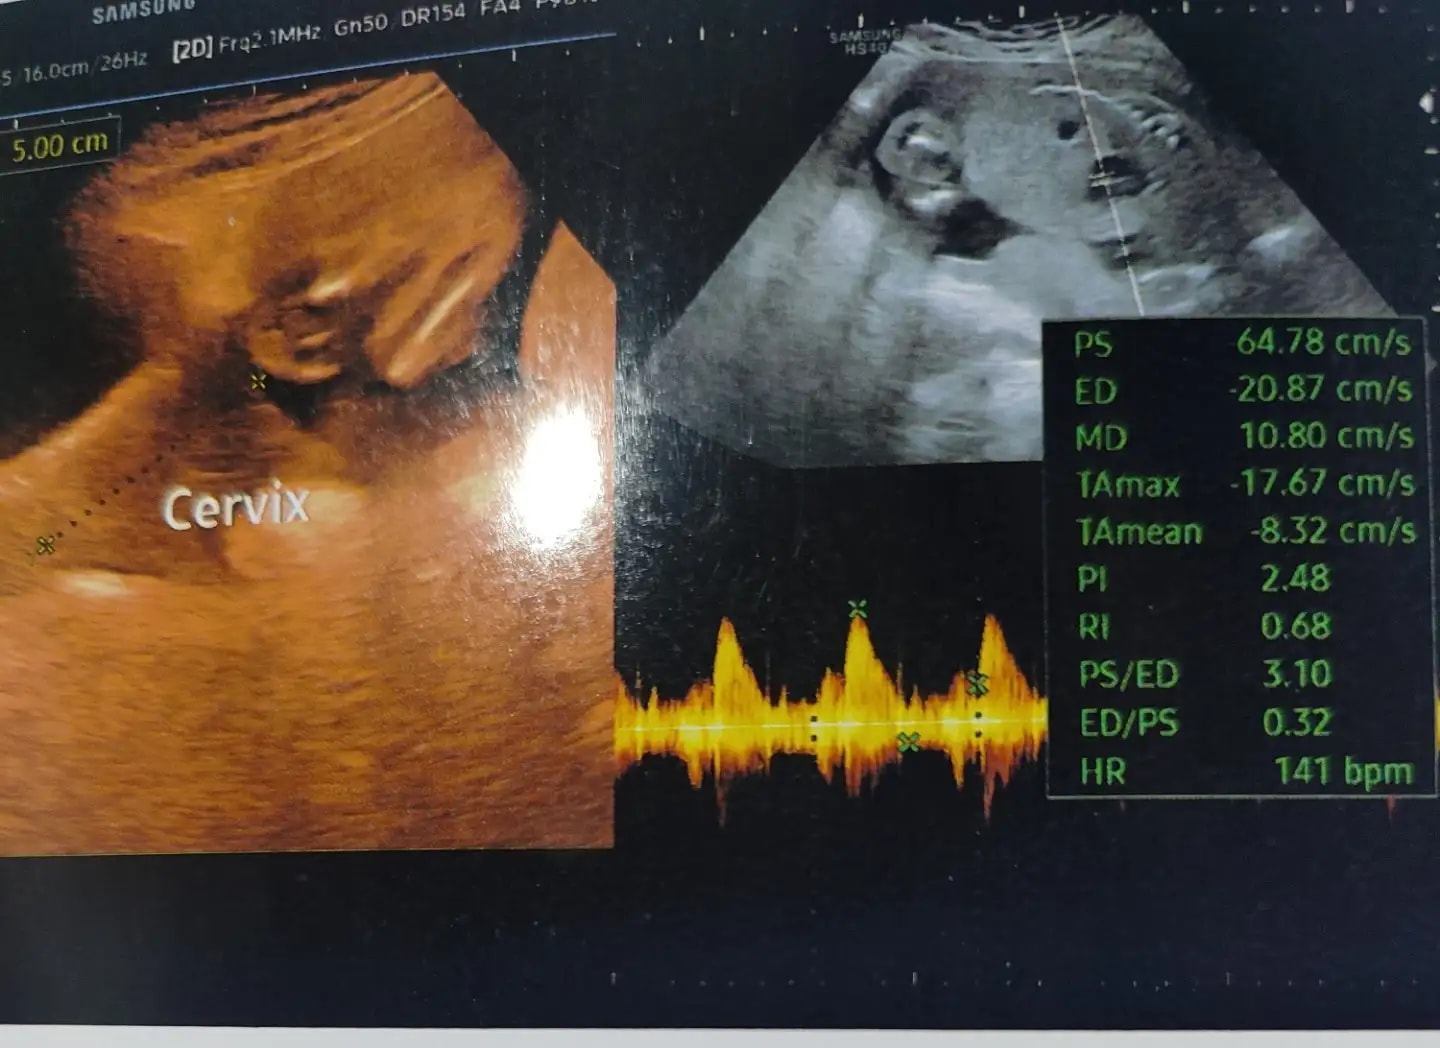

Q: What are these parameters....are they normal